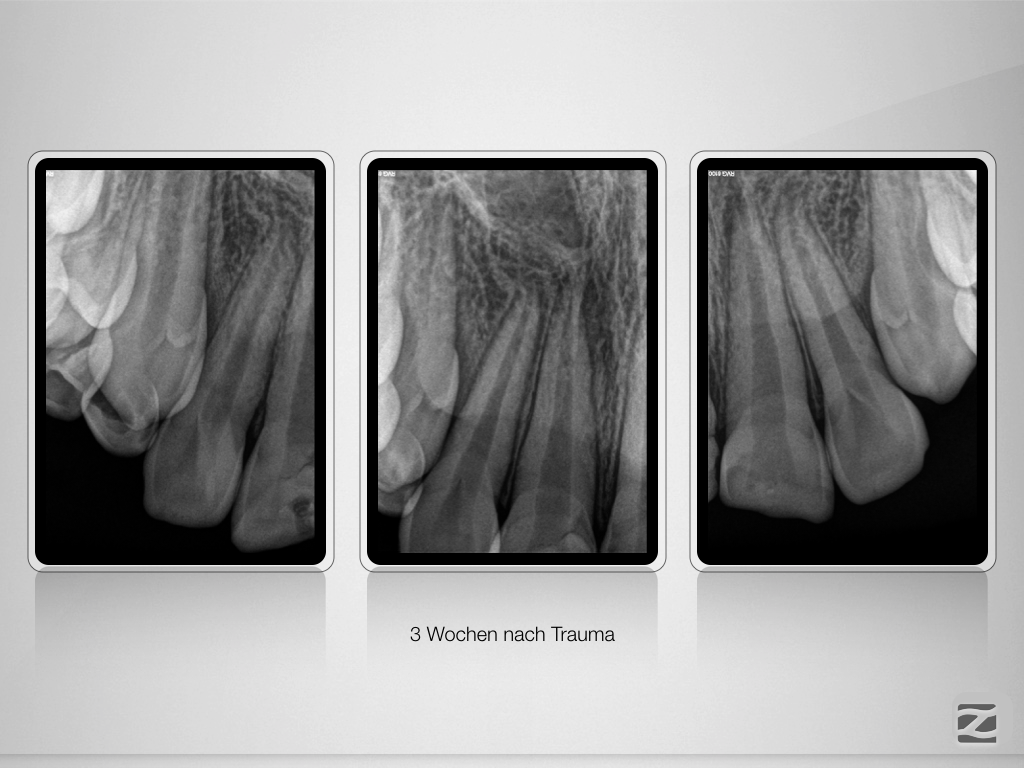

And the show goes on-Trauma, die Zweite.